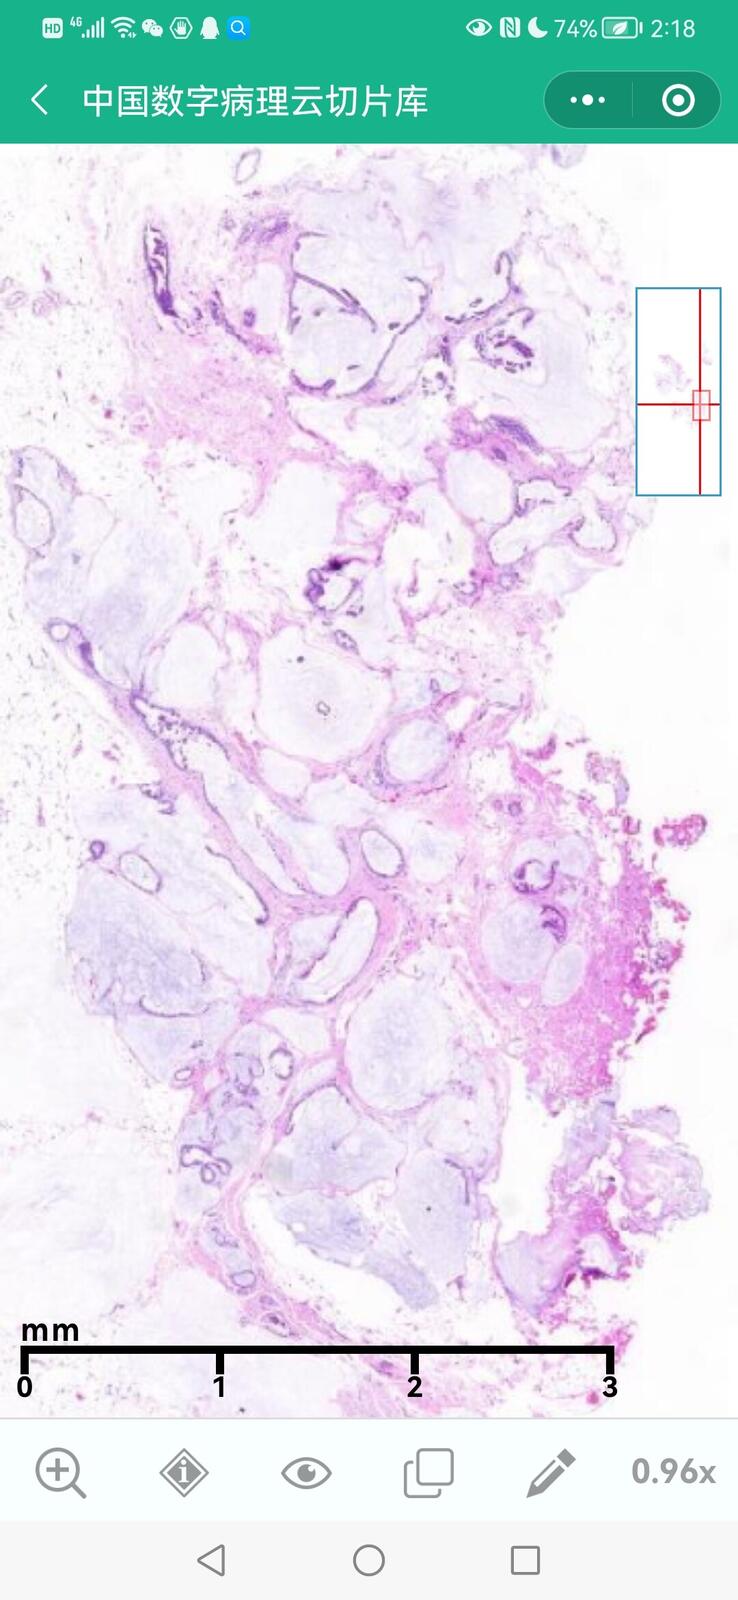

乳腺叶状囊肉瘤